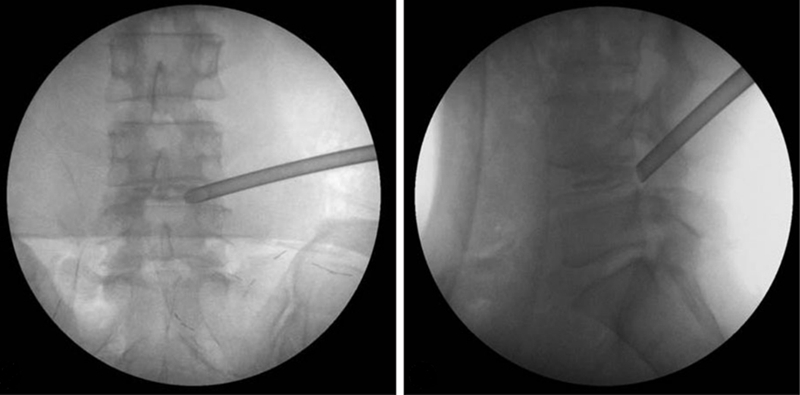

神经损伤又可分为出口根损伤和行走根损伤。有文献报道术中出口神经根损伤发生率约为1.0-8.9%,如果损伤出口根,其症状与术前症状不同,分布区域要比术前高一个节段。有学者认为其发生原因有二,一是局麻药物过量造成神经根麻木,置入工作通道时因病人感觉失常造成损伤,因此准确麻醉及穿刺置管是预防的关键;二是手术过程中工作通道压迫刺激出口根造成损伤。而走行根损伤多由术中不当操作引起,如暴力撕扯神经周围组织,在周围结构辨识不清的情况下贸然操作等等。

由于PTED技术学习曲线陡峭,早期手术出现神经损伤的并发症更高。在术前应结合每位患者的病情进行评估,决定术中具体的穿刺方式和路径;在穿刺置管过程中应小心谨慎,尤其是需要椎间孔成形操作的患者应在操作过程中时刻进行影像学透视监测,术中应仔细辨别组织解剖结构,特别是安全三角区,在减压取出髓核时询问患者有无下肢疼痛,防止暴力操作。